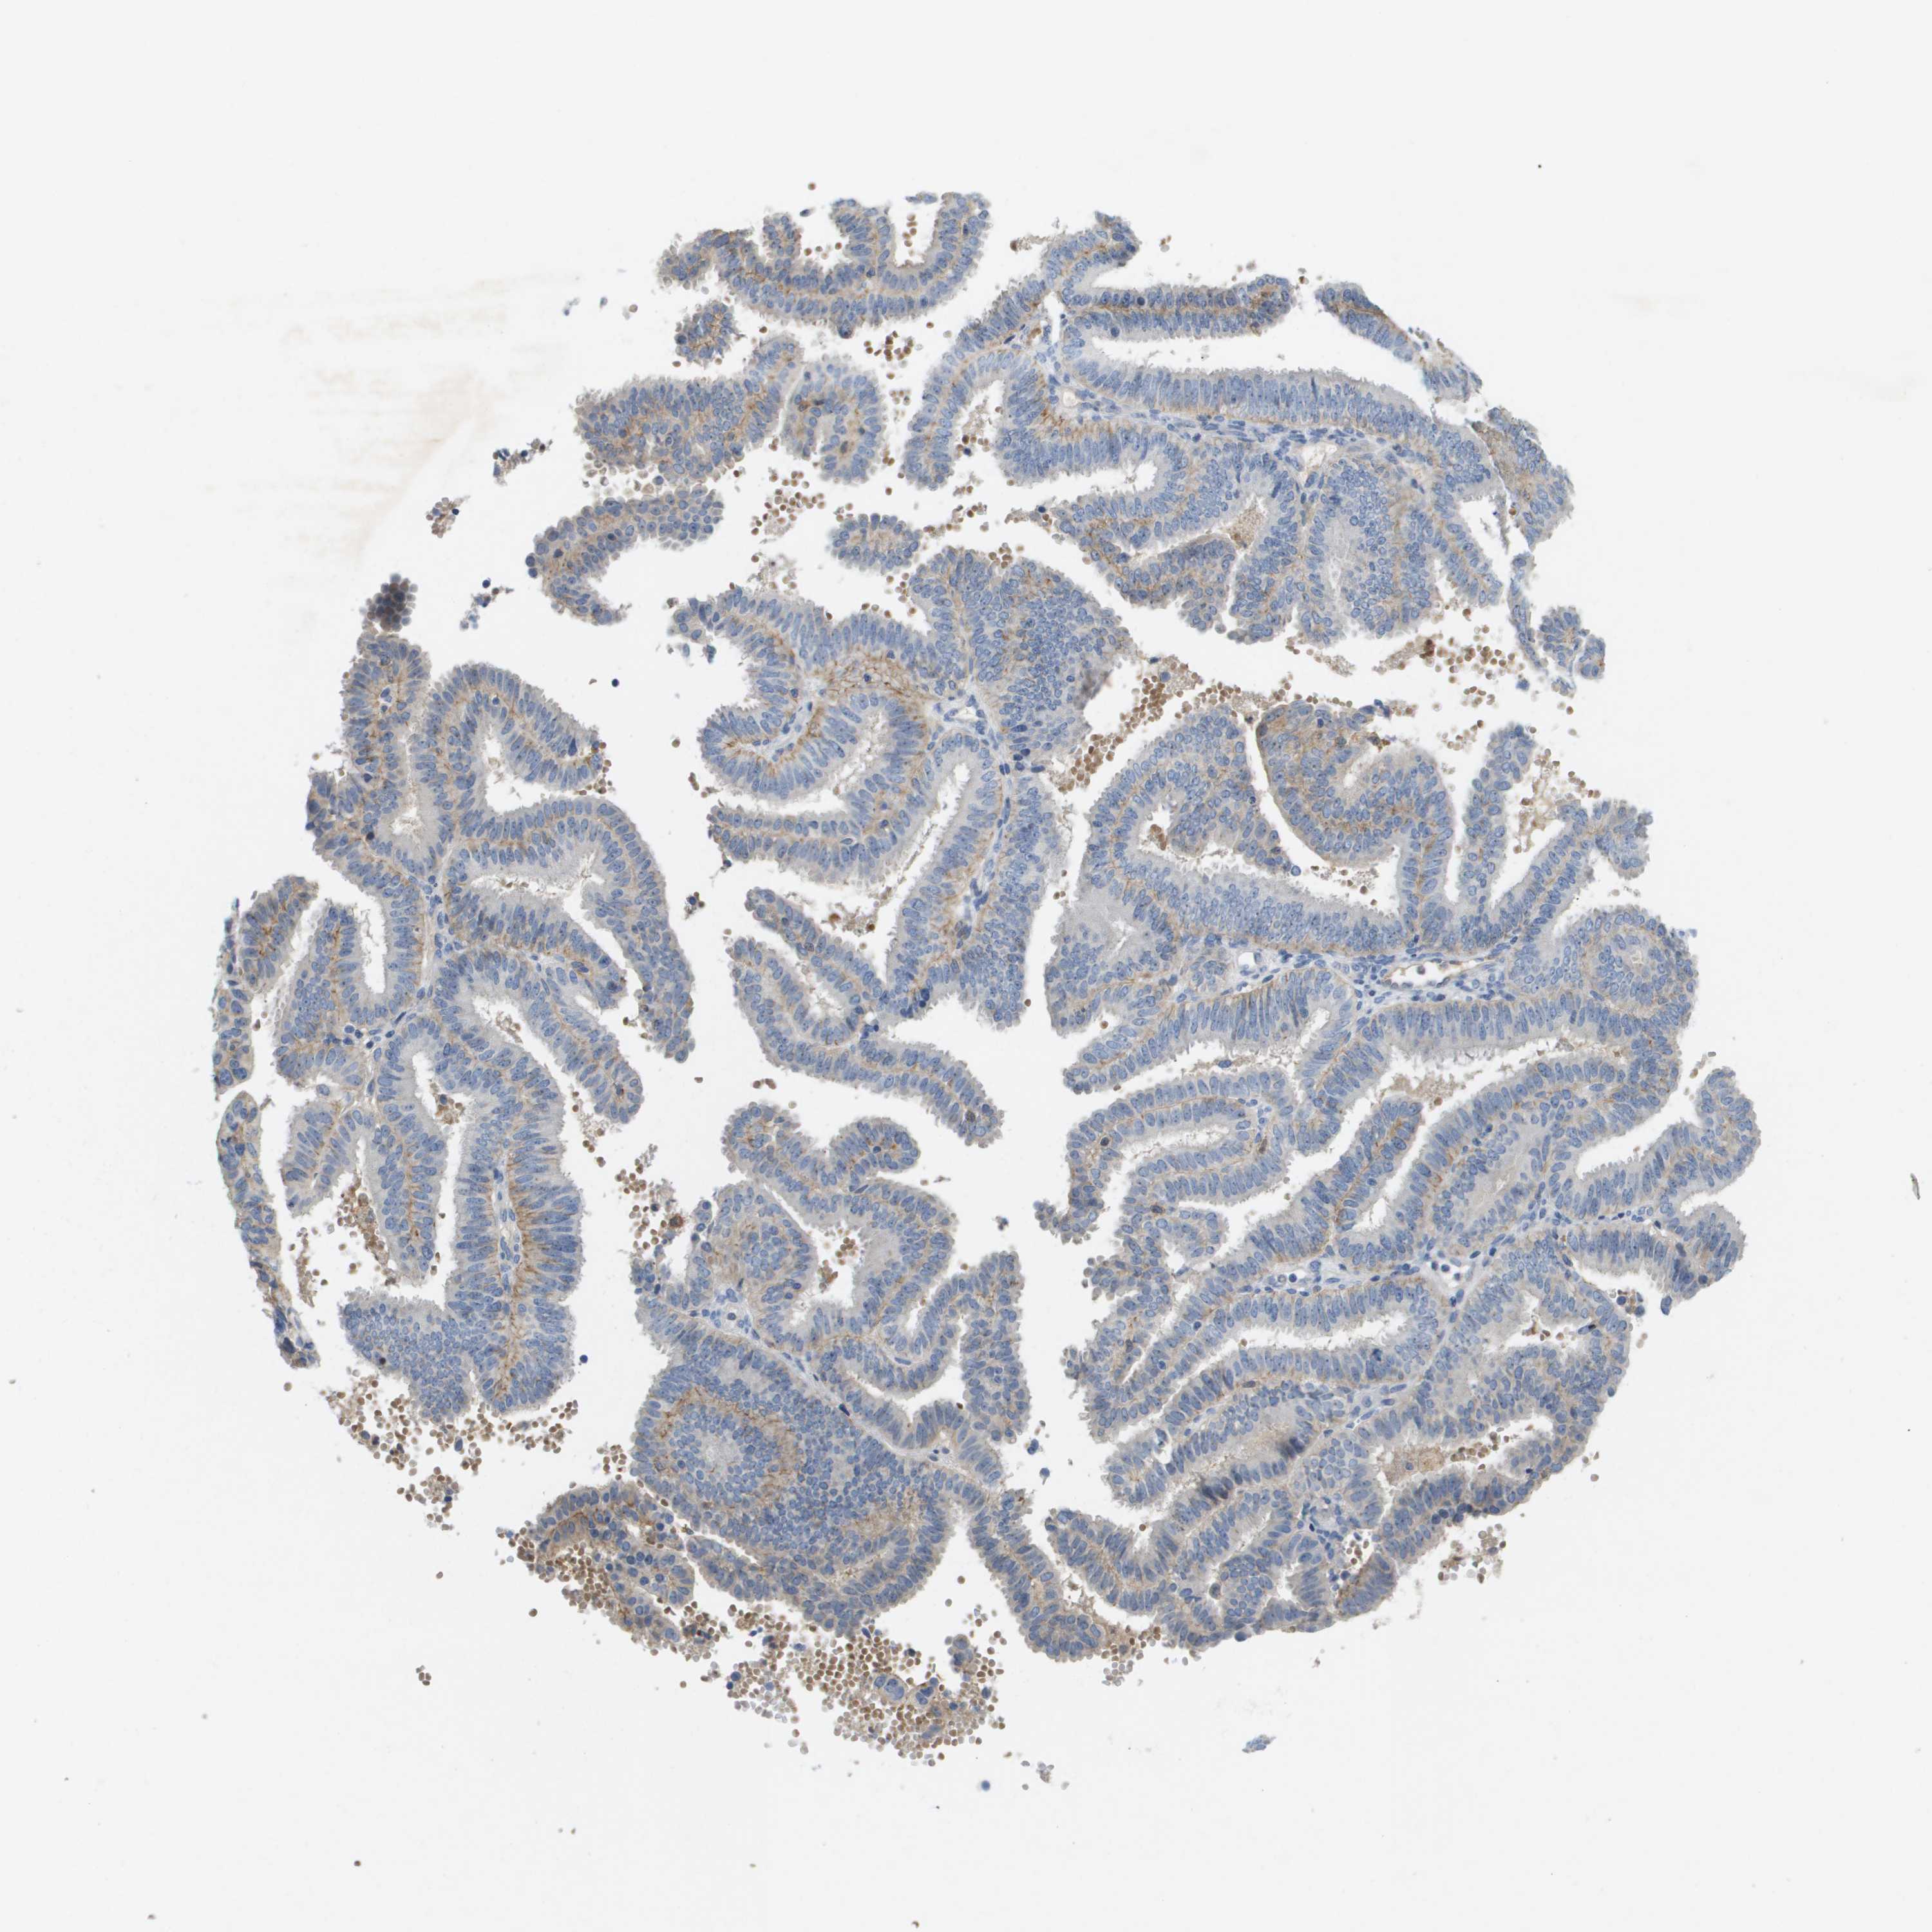

ENDOMETRIAL CANCER - Protein expressioni

A mouse-over function shows sample information and annotation data. Click on an image to view it in a full screen mode. Samples can be filtered based on level of antibody staining by selecting one or several of the following categories: high, medium, low and not detected. The assay and annotation is described here.

Note that samples used for immunohistochemistry by the Human Protein Atlas do not correspond to samples in the TCGA dataset.

Antibody stainingi

Antibody staining in the annotated cell types in the current human tissue is reported as not detected, low, medium, or high, based on conventional immunohistochemistry profiling in selected tissues. This score is based on the combination of the staining intensity and fraction of stained cells.

Each image is clickable and will lead to virtual microscopy that enables deeper exploration of all samples and also displays staining intensity scores, fraction scores and subcellular localization as well as patient and tissue information for each sample.

Antibody HPA016966

Staining

High

Medium

Low

Not detected

Intensity

Strong

Moderate

Weak

Negative

Quantity

>75%

75%-25%

<25%

None

Location

Nuclear

Cytoplasmic/membranous

Cytoplasmic/membranous,nuclear

Adenocarcinoma, NOS